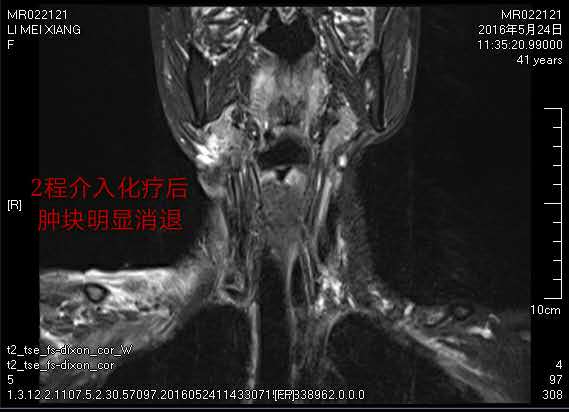

第一次介入治療后,腫瘤就縮小了一半,出血也逐漸停止,頸部潰爛的皮膚逐漸好轉(zhuǎn),為接下來的局部放療創(chuàng)造了條件。為鞏固治療,李大姐一共接受了三個療程的微創(chuàng)介入灌注治療,目前右頸部巨大腫塊已基本消退。治療后身體日漸康復(fù)的李大姐對未來充滿了信心。